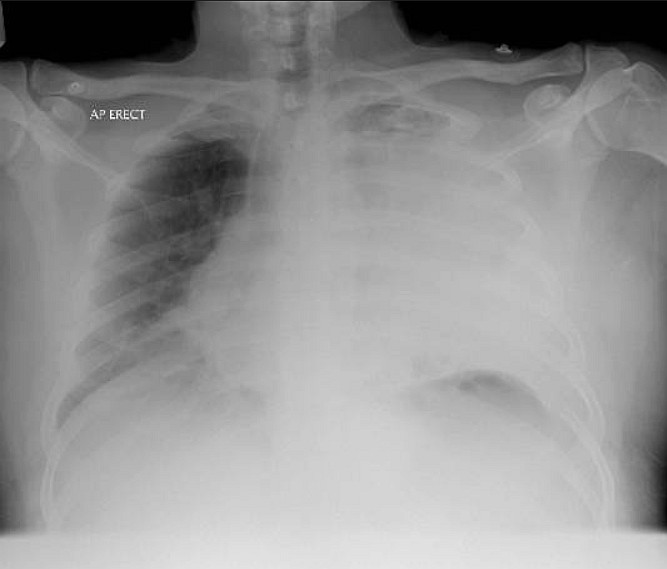

Imaging Findings

CXR revealed complete white out of left hemithorax and mediastinal shift to opposite side raising the possibility of massive pleural effusion or empyema. CT thorax revealed left pyopneumothorax.